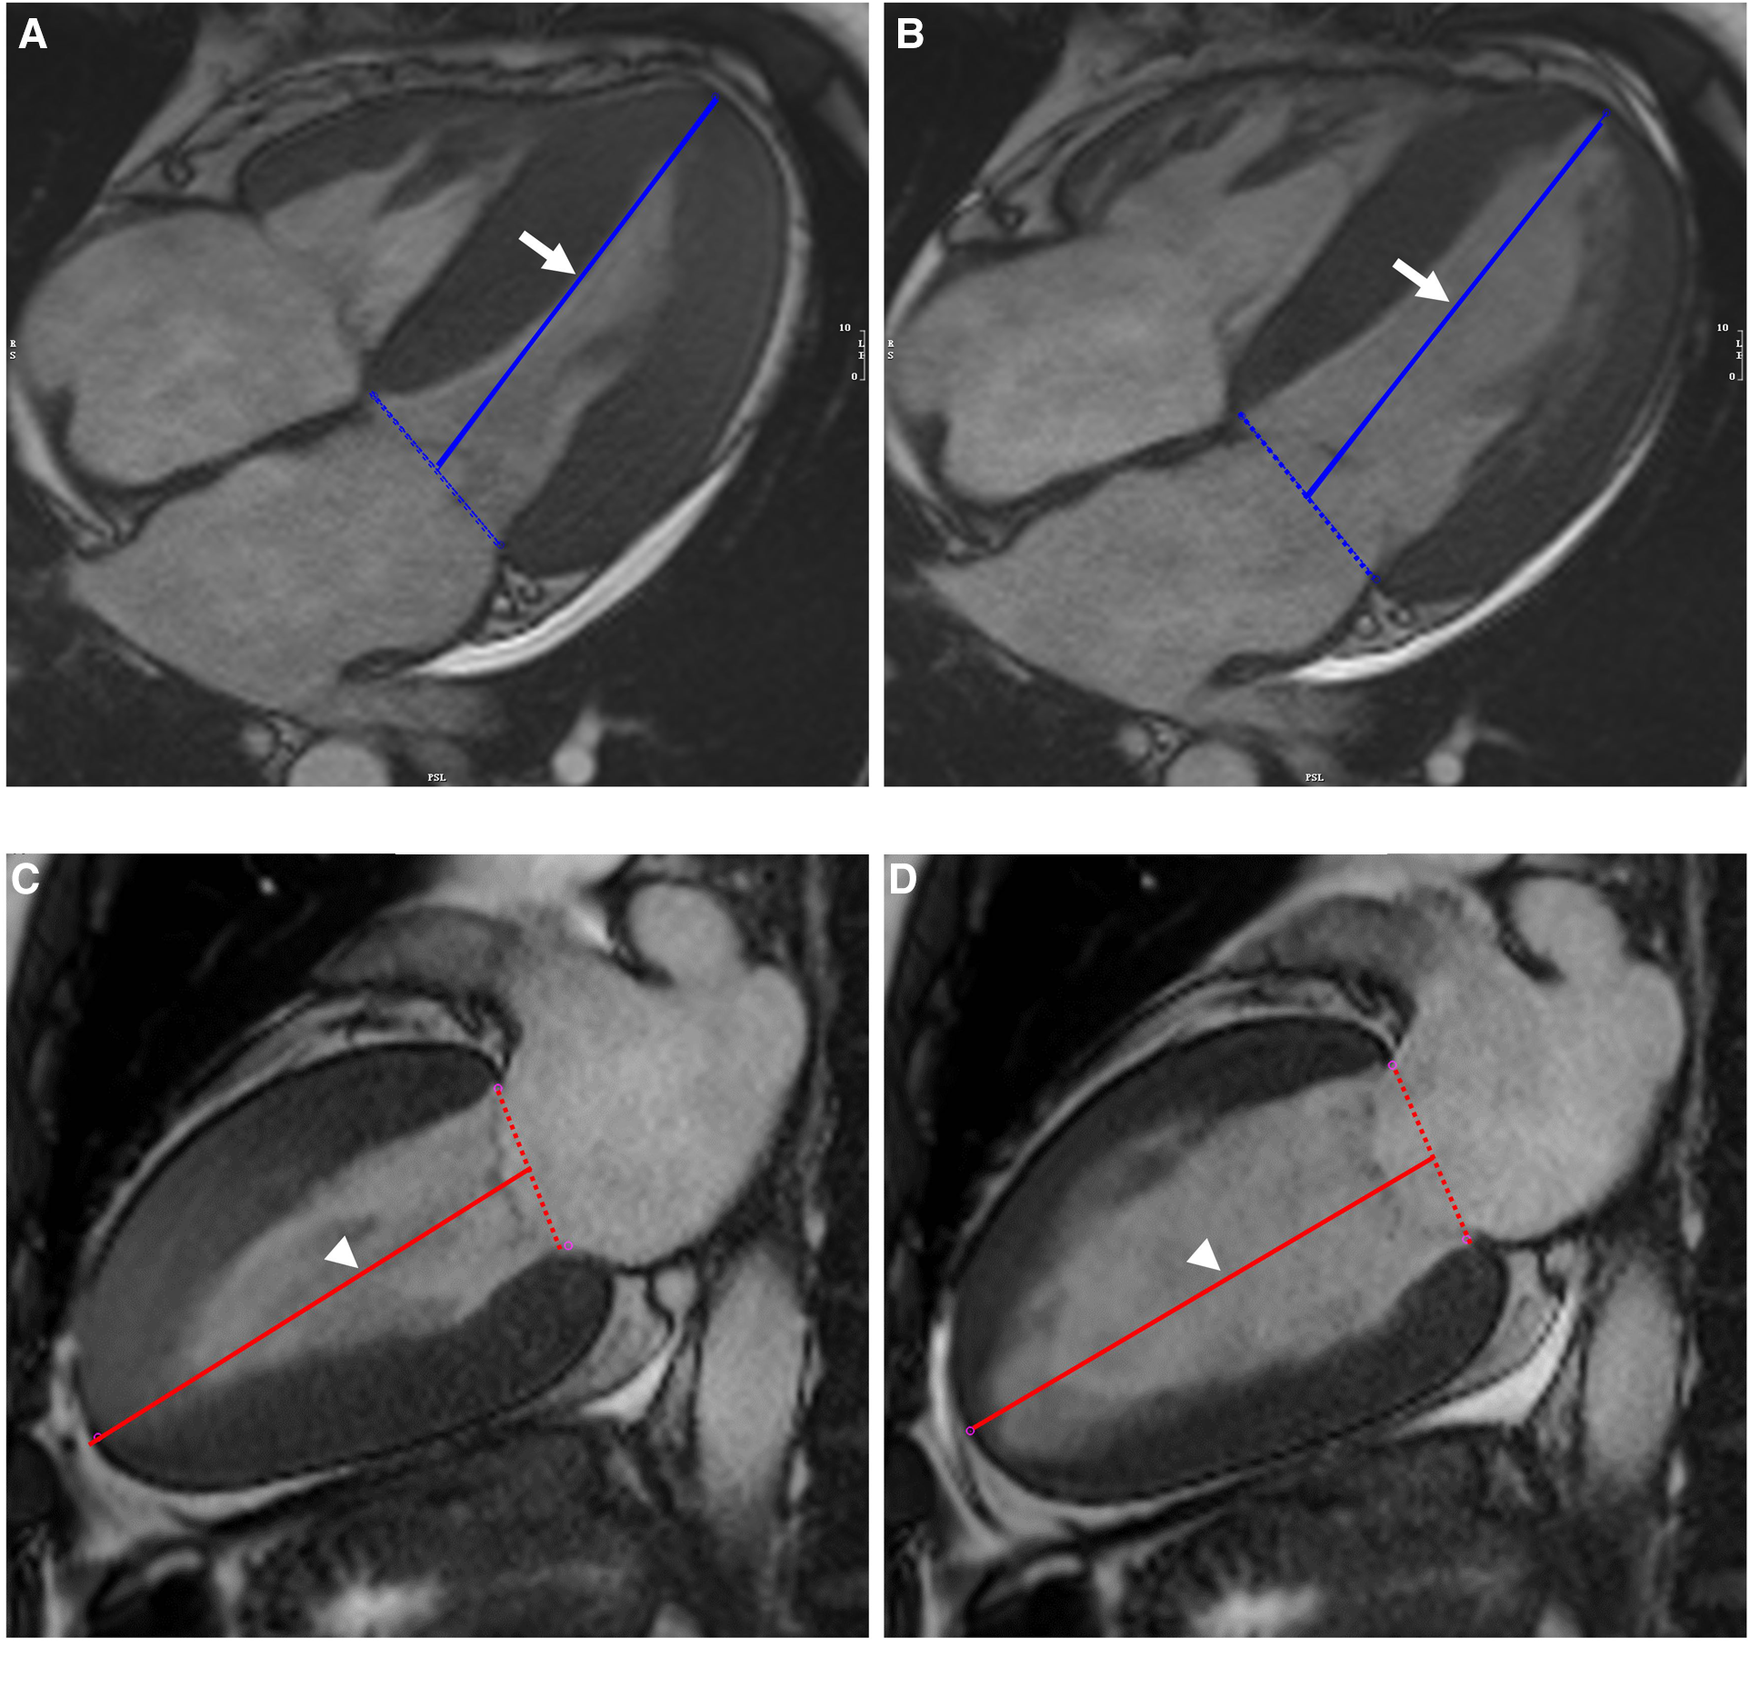

The left ventricular LAS was defined as the percentage of LV longitudinal axis shortening between the end-diastolic and end-systolic phases. The distance between the epicardial border of the LV apex and the center of a line that connects the origins of the mitral valve leaflets was measured in both the end-systolic and end-diastolic phases and defined as lengthend_syst and lengthend_diast, respectively. The percentage of LAS was then determined according to the following strain formula:The average of the measurements in the two-chamber and four-chamber views was used for the final analyses (Figure 1).

Figure 1

Illustration of biplanar assessment of LV LAS in an AL-CA patient on MR cine images: the solid blue line on end-systole (A) and end-diastole (B) of four-chamber view represented the distance between the epicardial border of the LV apex and the middle of a line connecting the origins of the mitral valves (white arrow). LV LAS was defined as the percentage in longitudinal shortening of the LV between end-diastole and end-systole. The measurements were performed on end-systole (C) and end-diastole (D) of two-chamber view and were shown as solid red line (white arrowhead). The average of the two LAS values was taken. LV, left ventricular; LAS, long-axis strain; AL-CA, light-chain patients with cardiac amyloidosis.